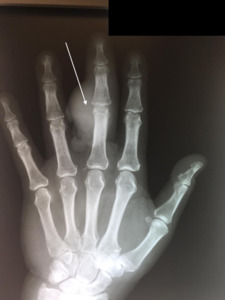

In addition, evaluation revealed a raised dorsal hand mass near the wrist crease with ulceration. Two PA (Posterior-Anterior) and lateral radiographs (i.e., x-rays) of the left hand, taken at this time, demonstrated a radiopaque bone lesion on the ulnar aspect of the dorsal third digit, centered on the proximal interphalangeal (PIP) joint (Figures 1, 2). Magnetic resonance imaging (MRI) was obtained to assess for local osseous (i.e., bony) invasion. NOTE: The patient authorized the publication of all radiographic and photographic figures that will appear in this paper.